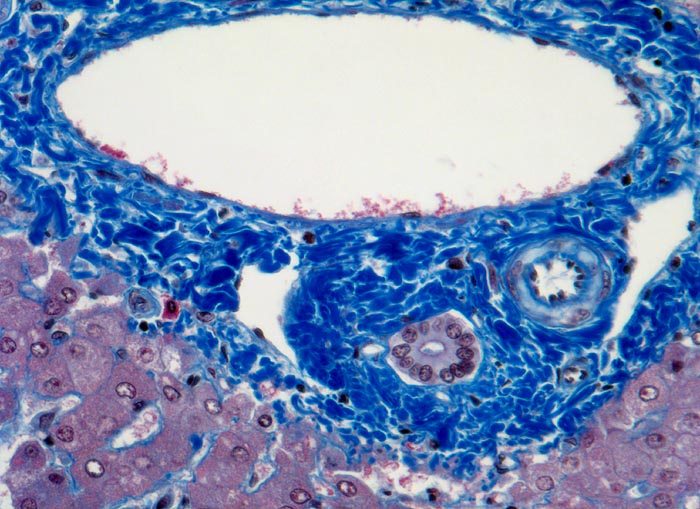

Meist findet sich eine grobtropfige oder gemischttropfige Verfettung des Parenchyms. Schon im Frühstadium der alkoholischen Steatohepatitis kann eine perizelluläre Maschendrahtfibrose, perisinusoidale und perivenuläre Fibrose mit Beginn in der Zone 3 festgestellt werden. Die Kombination von perivenulärer und perizellulärer (> 1096) Fibrose wird bei starker Ausprägung mit Arealen von dichter Kollagenfaserbildung auch als zentrale sklerosierende hyaline Nekrose bezeichnet. Wenn der Vernarbungsprozess fortschreitet, kann die perivenuläre Fibrosezone mit vernarbten Portalfeldern verschmelzen. Zentralvenen verschwinden oder sind stark in der Anzahl reduziert. Eine Phlebosklerose oder Obliteration der Zentralvenen kann hinzukommen. Breite Bänder von fibrotischem Gewebe mit Ductulusproliferationen und gemischtem Entzündungsinfiltrat umgeben die bei alkohlischer Zirrhose meist kleinen Regeneratknoten (=mikronoduläre Leberzirrhose mit Regeneratknoten von weniger als 3mm Durchmesser). Bei längeren Abstinenzphasen kann sich aufgrund der gesteigerten Regeneration auch eine gemischtknotige Zirrhose ausbilden. Ein gleichzeitiges Vorliegen einer Steatose oder Steatohepatitis (Steatose+neutrophile Granulozyten) in einer alkoholischen Leberzirrhose signalisiert in der Regel einen fortgesetzten Aethylabusus. Typisch für alkoholtoxische Leberschädigung sind Mallory-Denk Körperchen (> 3021), Megamitochondrien (> 3022) und eine Zellschwellung (=Ballonierung) aufgrund einer gestörten Albuminausschleusung. Oft können mässige Mengen von Hämosiderinablagerungen vor allem in den Kupffer Zellen nachgewiesen werden. Weitgehend identische morphologische Veränderungen wie bei der aethylischen Leberschädigung finden sich auch bei der nicht alkoholischen Steatohepatitis (NASH) d.h. bei Patienten, die keinen oder nur wenig Alkohol konsumieren.

• Perivenuläre Fibrose und perizelluläre Maschendrahtfibrose in Zone 3.

• Verminderte Anzahl Zentralvenen.

• Mallory-Denk Körperchen